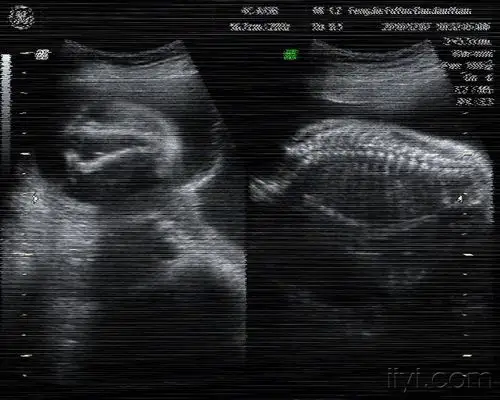

一无脑儿b超图片

无脑儿:郭某 24岁 孕28周,早孕外院超声"无异常".